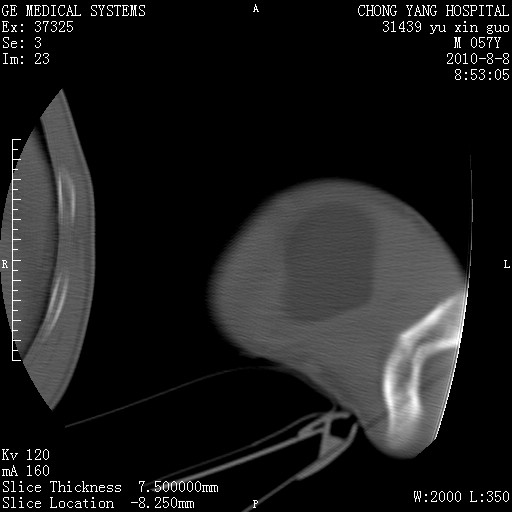

标题: CT28267:M57Y 上臂包块8年余。 [打印本页]

标题: CT28267:M57Y 上臂包块8年余。

包膜光滑、完整的脂肪密度肿块,支持脂肪瘤。